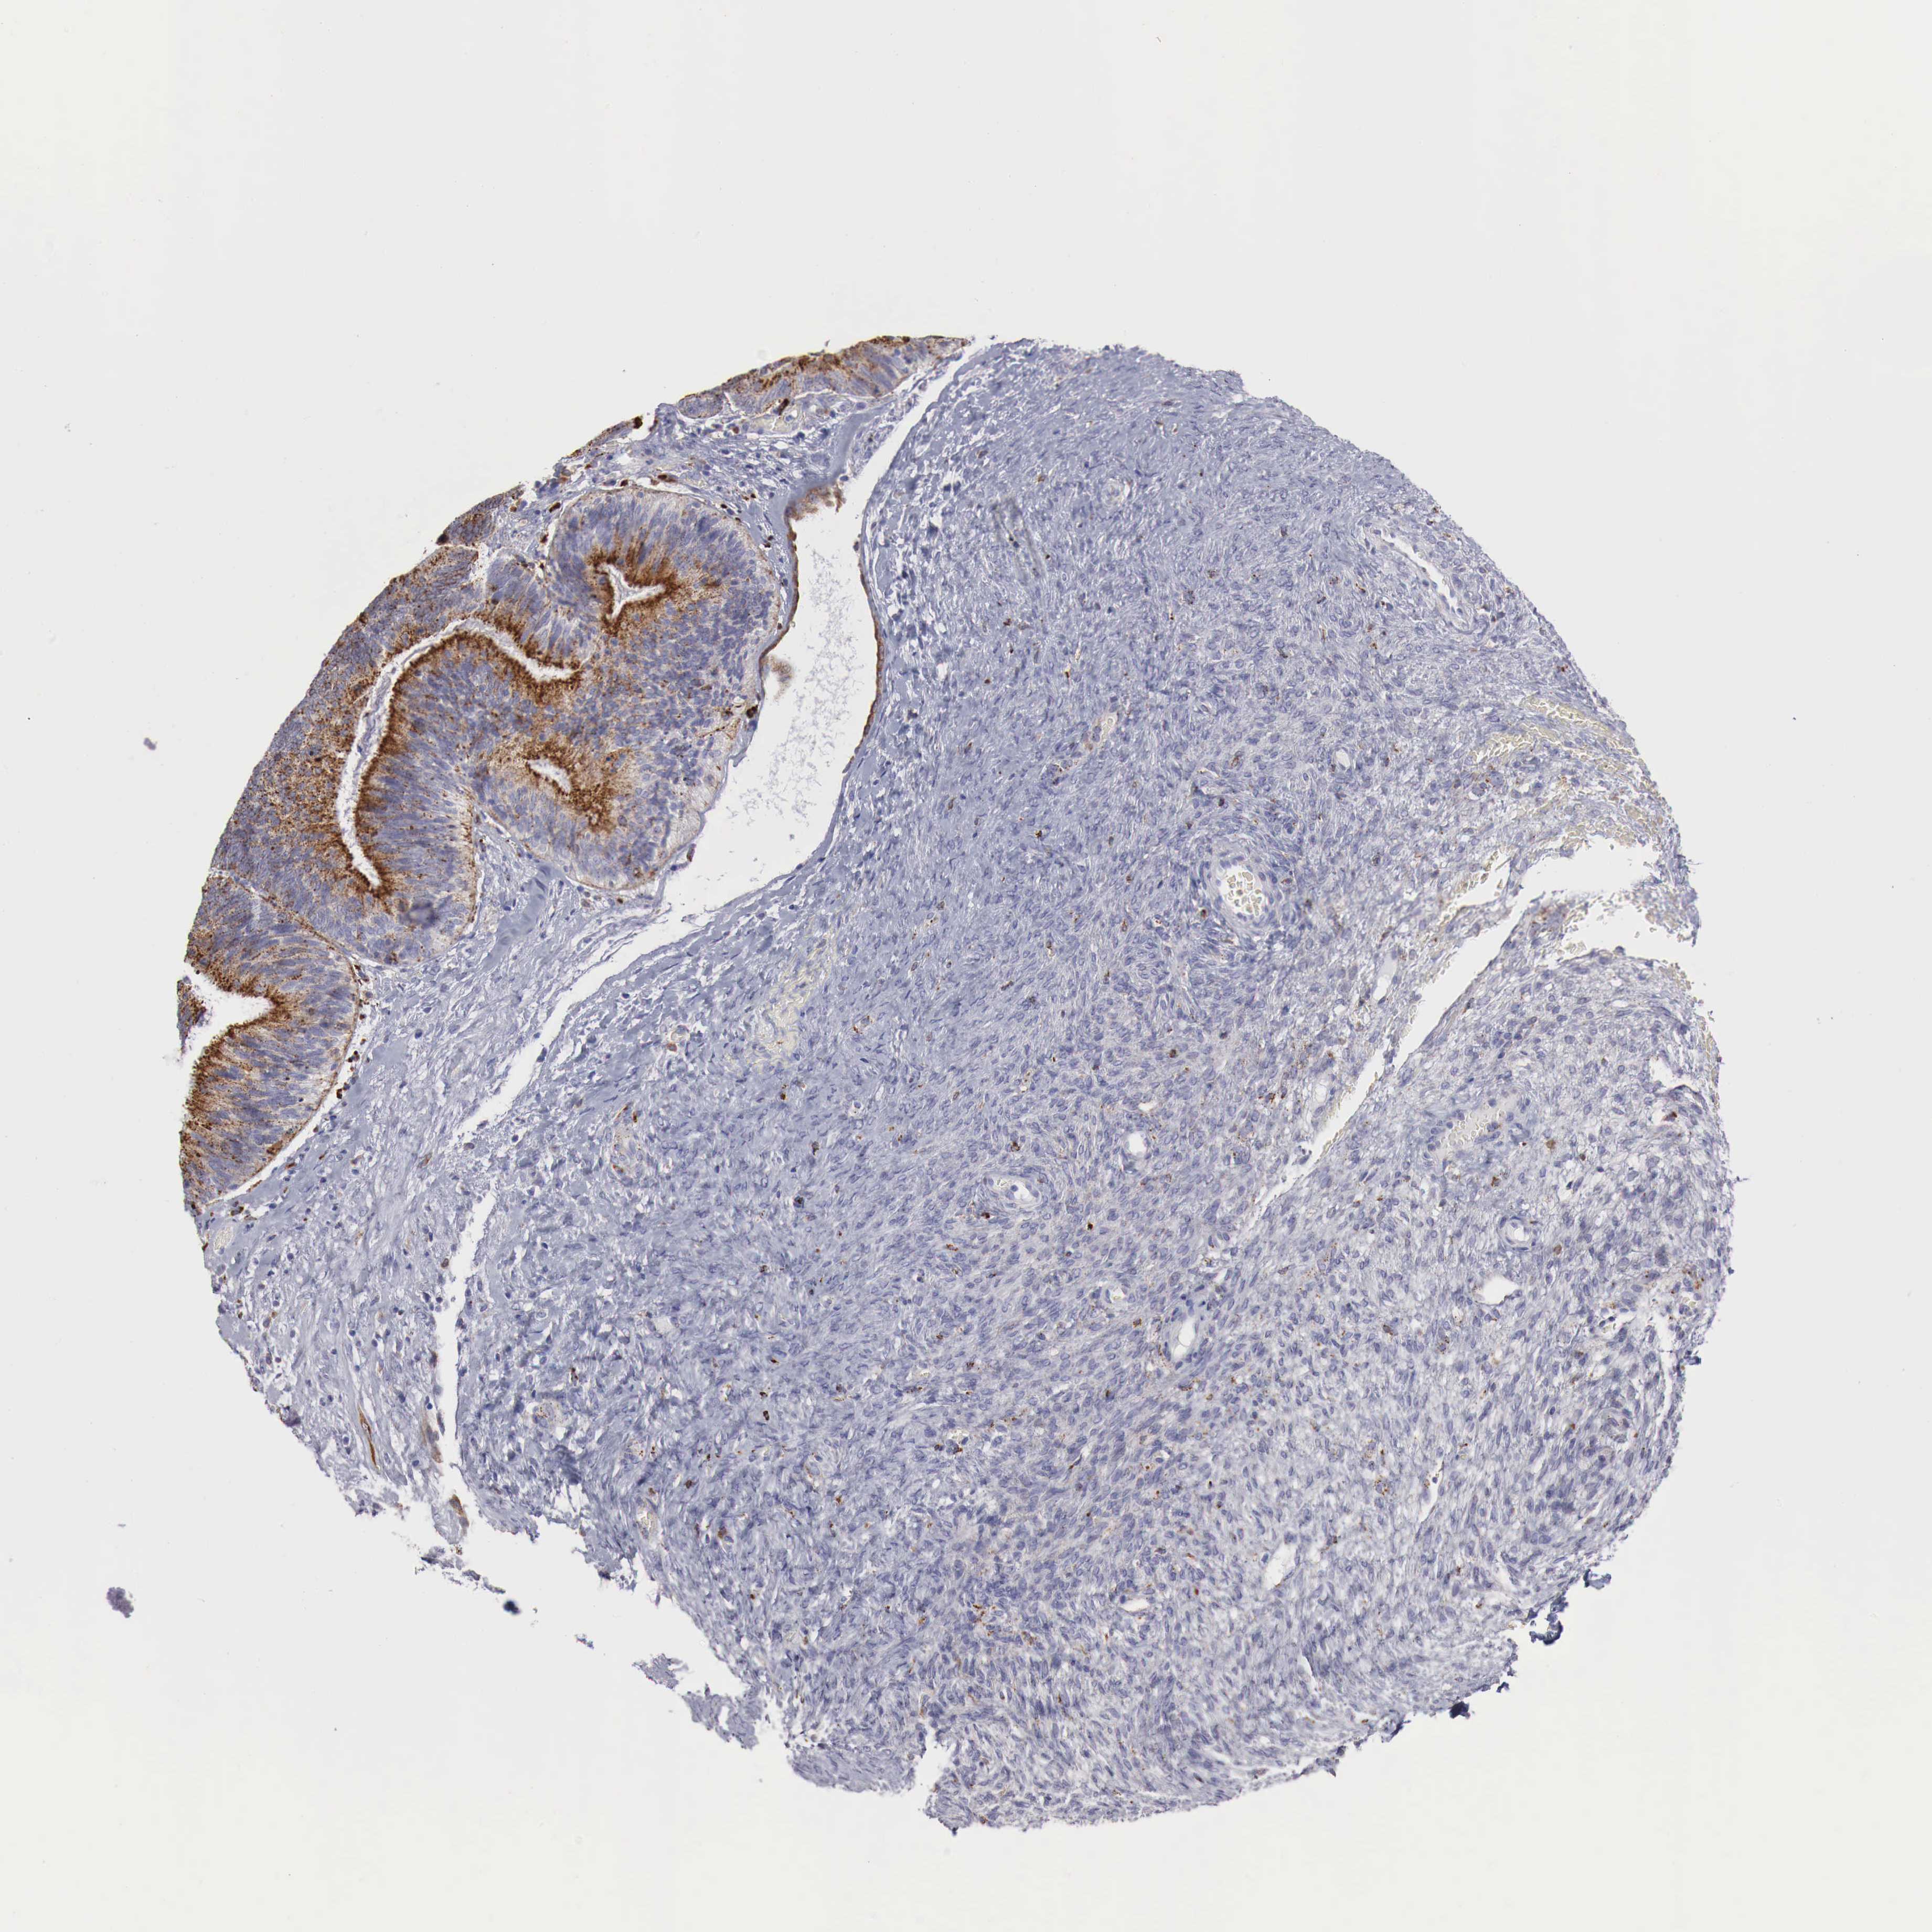

OVARIAN CANCER - Protein expressioni

A mouse-over function shows sample information and annotation data. Click on an image to view it in a full screen mode. Samples can be filtered based on level of antibody staining by selecting one or several of the following categories: high, medium, low and not detected. The assay and annotation is described here.

Note that samples used for immunohistochemistry by the Human Protein Atlas do not correspond to samples in the TCGA dataset.

Antibody stainingi

Antibody staining in the annotated cell types in the current human tissue is reported as not detected, low, medium, or high, based on conventional immunohistochemistry profiling in selected tissues. This score is based on the combination of the staining intensity and fraction of stained cells.

Each image is clickable and will lead to virtual microscopy that enables deeper exploration of all samples and also displays staining intensity scores, fraction scores and subcellular localization as well as patient and tissue information for each sample.

Antibody HPA000237

Antibody HPA000966

Staining

High

Medium

Low

Not detected

Intensity

Strong

Moderate

Weak

Negative

Quantity

>75%

75%-25%

<25%

None

Location

Nuclear

Cytoplasmic/membranous

Cytoplasmic/membranous,nuclear

Cystadenocarcinoma, mucinous, NOS

Carcinoma, endometroid

Cystadenocarcinoma, serous, NOS